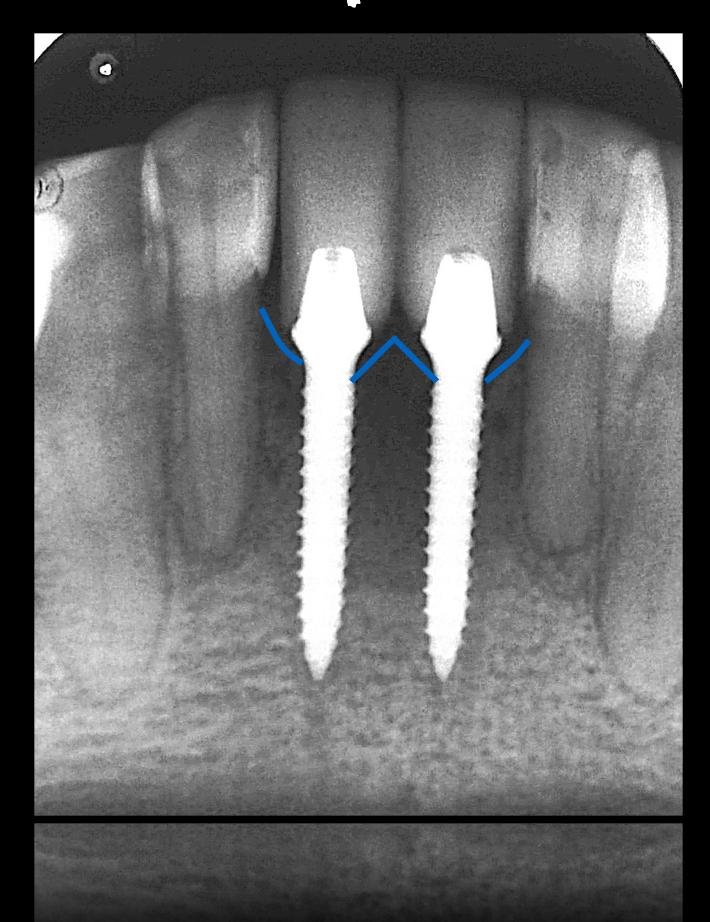

Como é necessário sempre reconstruir a parede vestibular, sua integridade não se faz necessária. Manfro et al (2019) propuseram uma classificação para esta perda e de acordo com essa classificação modificações para a técnica cirúrgica.

Classe 1: parede vestibular íntegra: nesta situação não existe necessidade de mudar a técnica, sendo necessário a construção de um GAP de 3mm que deve ser enxertado com substituto ósseo de lenta degradação.

Classe 2: esta situação é caracterizada pela perda de até 1/3 da tábua óssea vestibular. Nesta situação, o contorno do alvéolo ainda é mantido. Nesta situação, acreditamos que a melhor maneira de fazer a técnica é seguir esta sequência após a exodontia e avaliação dos alvéolos: